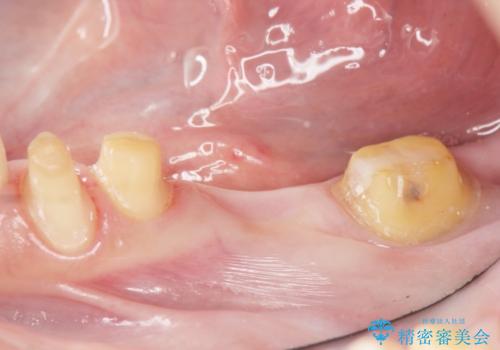

銀歯のブリッジをジルコニアブリッジへ

- 笑った時に大きく見えてしまう奥歯の銀歯ブリッジを白くしたいと希望され来院されました。

強度があり、審美性にも優れるジルコニアブリッジに置き替えていく治療計画としました。

- 39.6万円(ジルコニアクラウン×3・仮歯×3)費用は治療当時の料金となります